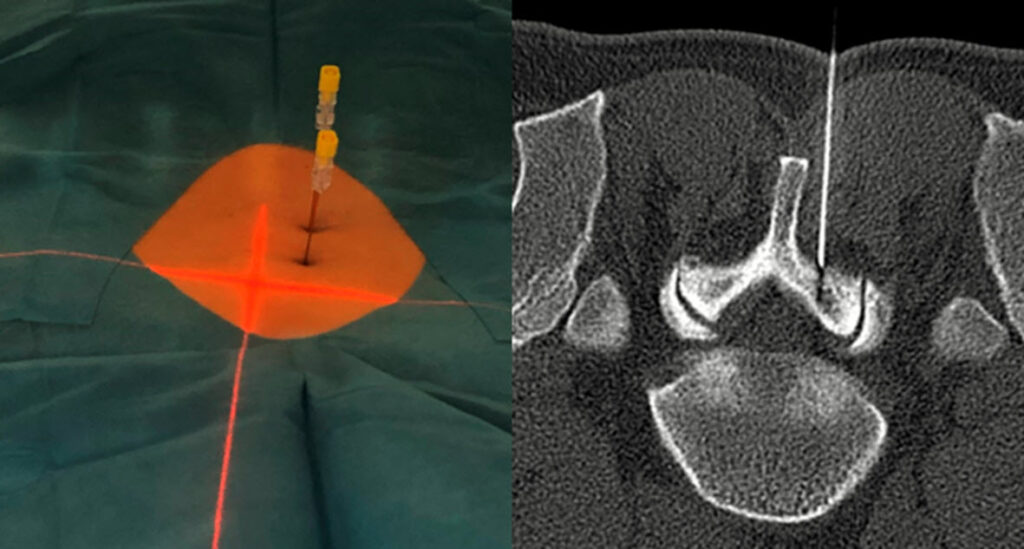

Das 0.55 Tesla MRT reduziert störende Bildverzerrungen durch Metallimplantate wie Prothesen oder Schrauben.

Das MRT eignet sich besonders gut, um frühzeitig Lockerungen von Prothesen oder Schrauben zu erkennen. Es kann feinste Veränderungen an der Knochenstruktur oder an den Implantaten nachweisen, die auf eine Lockerung hinweisen könnten.